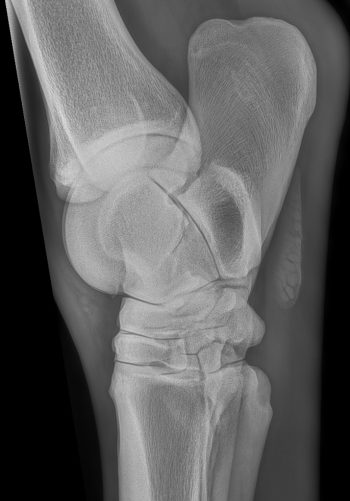

3- Examen des membres antérieurs et postérieurs dans le cas de boiterie, de fracture, d’exploration d’une masse.

4- Examen du bassin, suivant le format de l’animal, dans l’exploration des boiteries hautes, défauts de propulsion et/ou d’engagement des postérieurs.